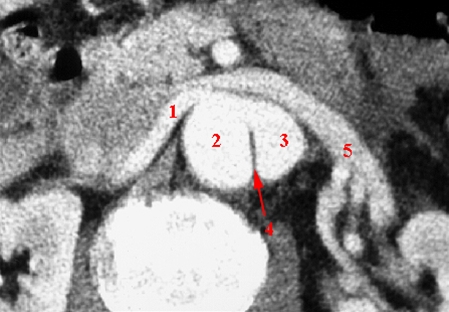

Øverste billede er et tværsnit (axial billede) af aorta med kontrast. Snit gennem aorta i niveau med højre nyrearterie.

- Højre nyrearterie

- Falskt lumen i aorta

- Sande lumen i aorta

- Dissektionsmembran/ løsnet intima

- Venstre nyrevene